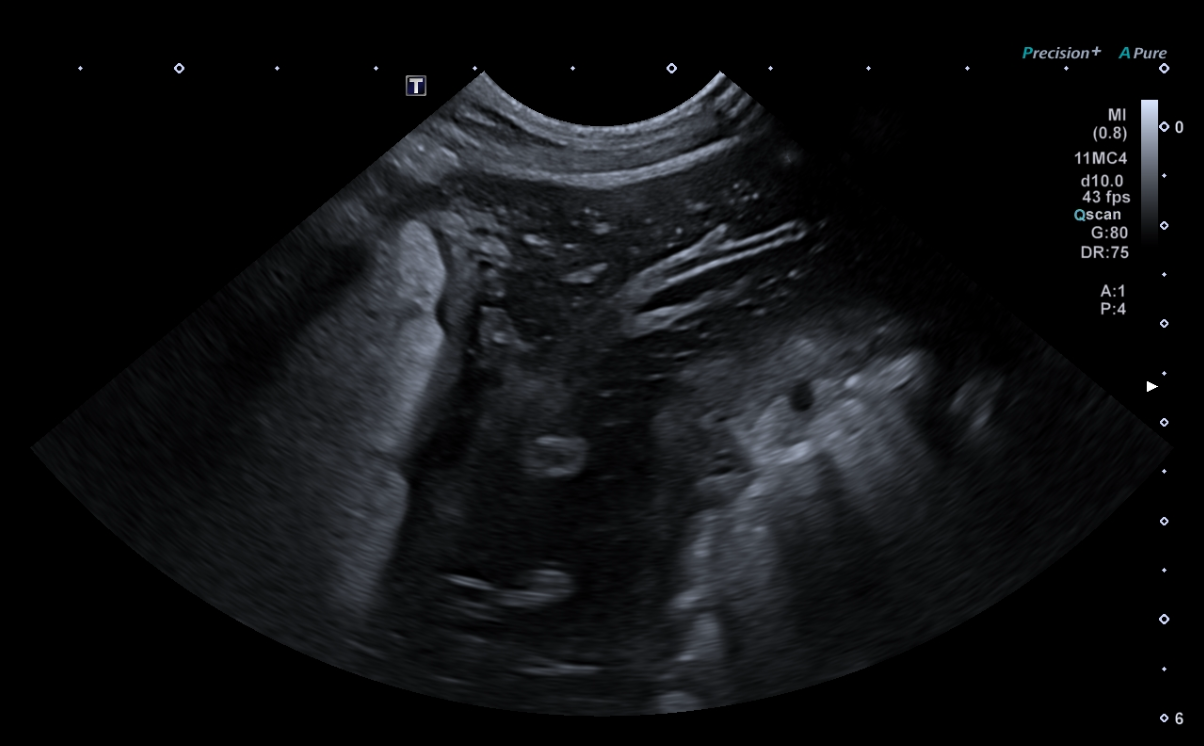

Exposé théorique (par vidéoprojection) de sémiologie échographique explicitant les signes à rechercher et l'interprétation des principales lésions hépatiques et spléniques.

Apprentissage d'un raisonnement échographique à partir de vidéos de cas cliniques pathologiques du foie et de la rate : Identification de la lésion, description avec les termes appropriés, synthèse des anomalies observées et diagnostic différentiel.